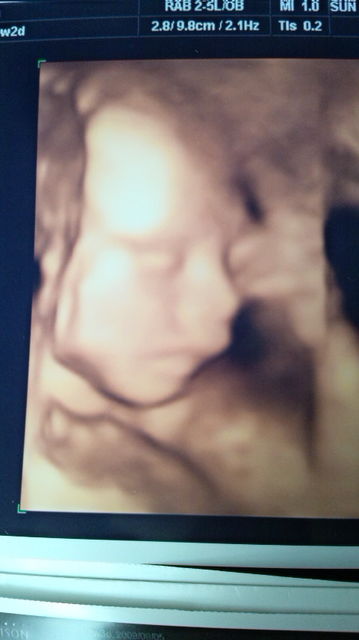

本日21w2dの次男坊

推定体重は498gでした

ちなみに22w3dの秀敏

推定体重616g

なんだか似てるぞ…またしても父ちゃん似なのか